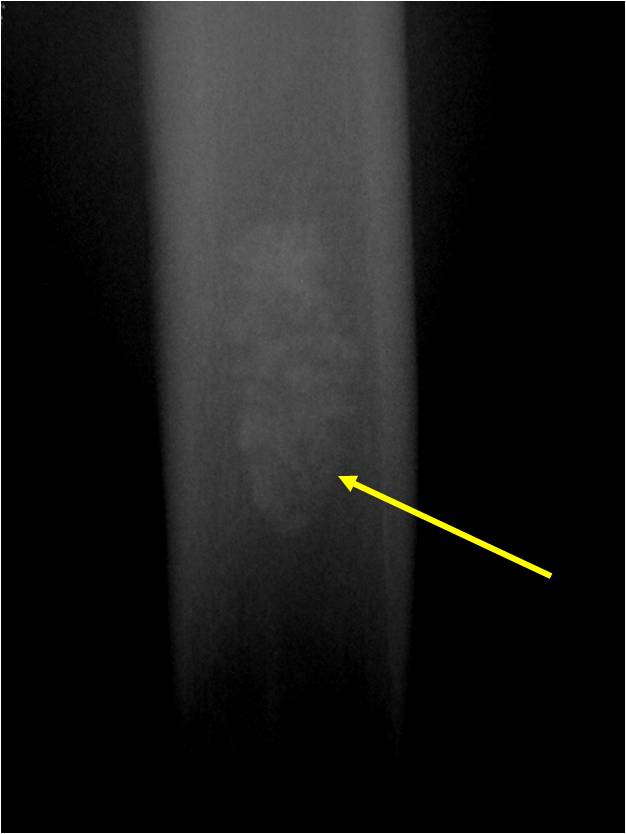

Plain X-Ray:

- Geographic lytic lesion

- Central often metaphyseal in long bones

- Can be eccentric also

- Expansile remodeling with thinned cortex

- Chondroid matrix with calcifications in majority of tumors

- Approximately 20% have limited or no calcifications

Ring and Arc Calcifications, Minimal Endosteal Scalloping, Cortex Intact, No Soft Tissue Component, No Periosteal Reaction

Minimal Endosteal Scalloping is Acceptable